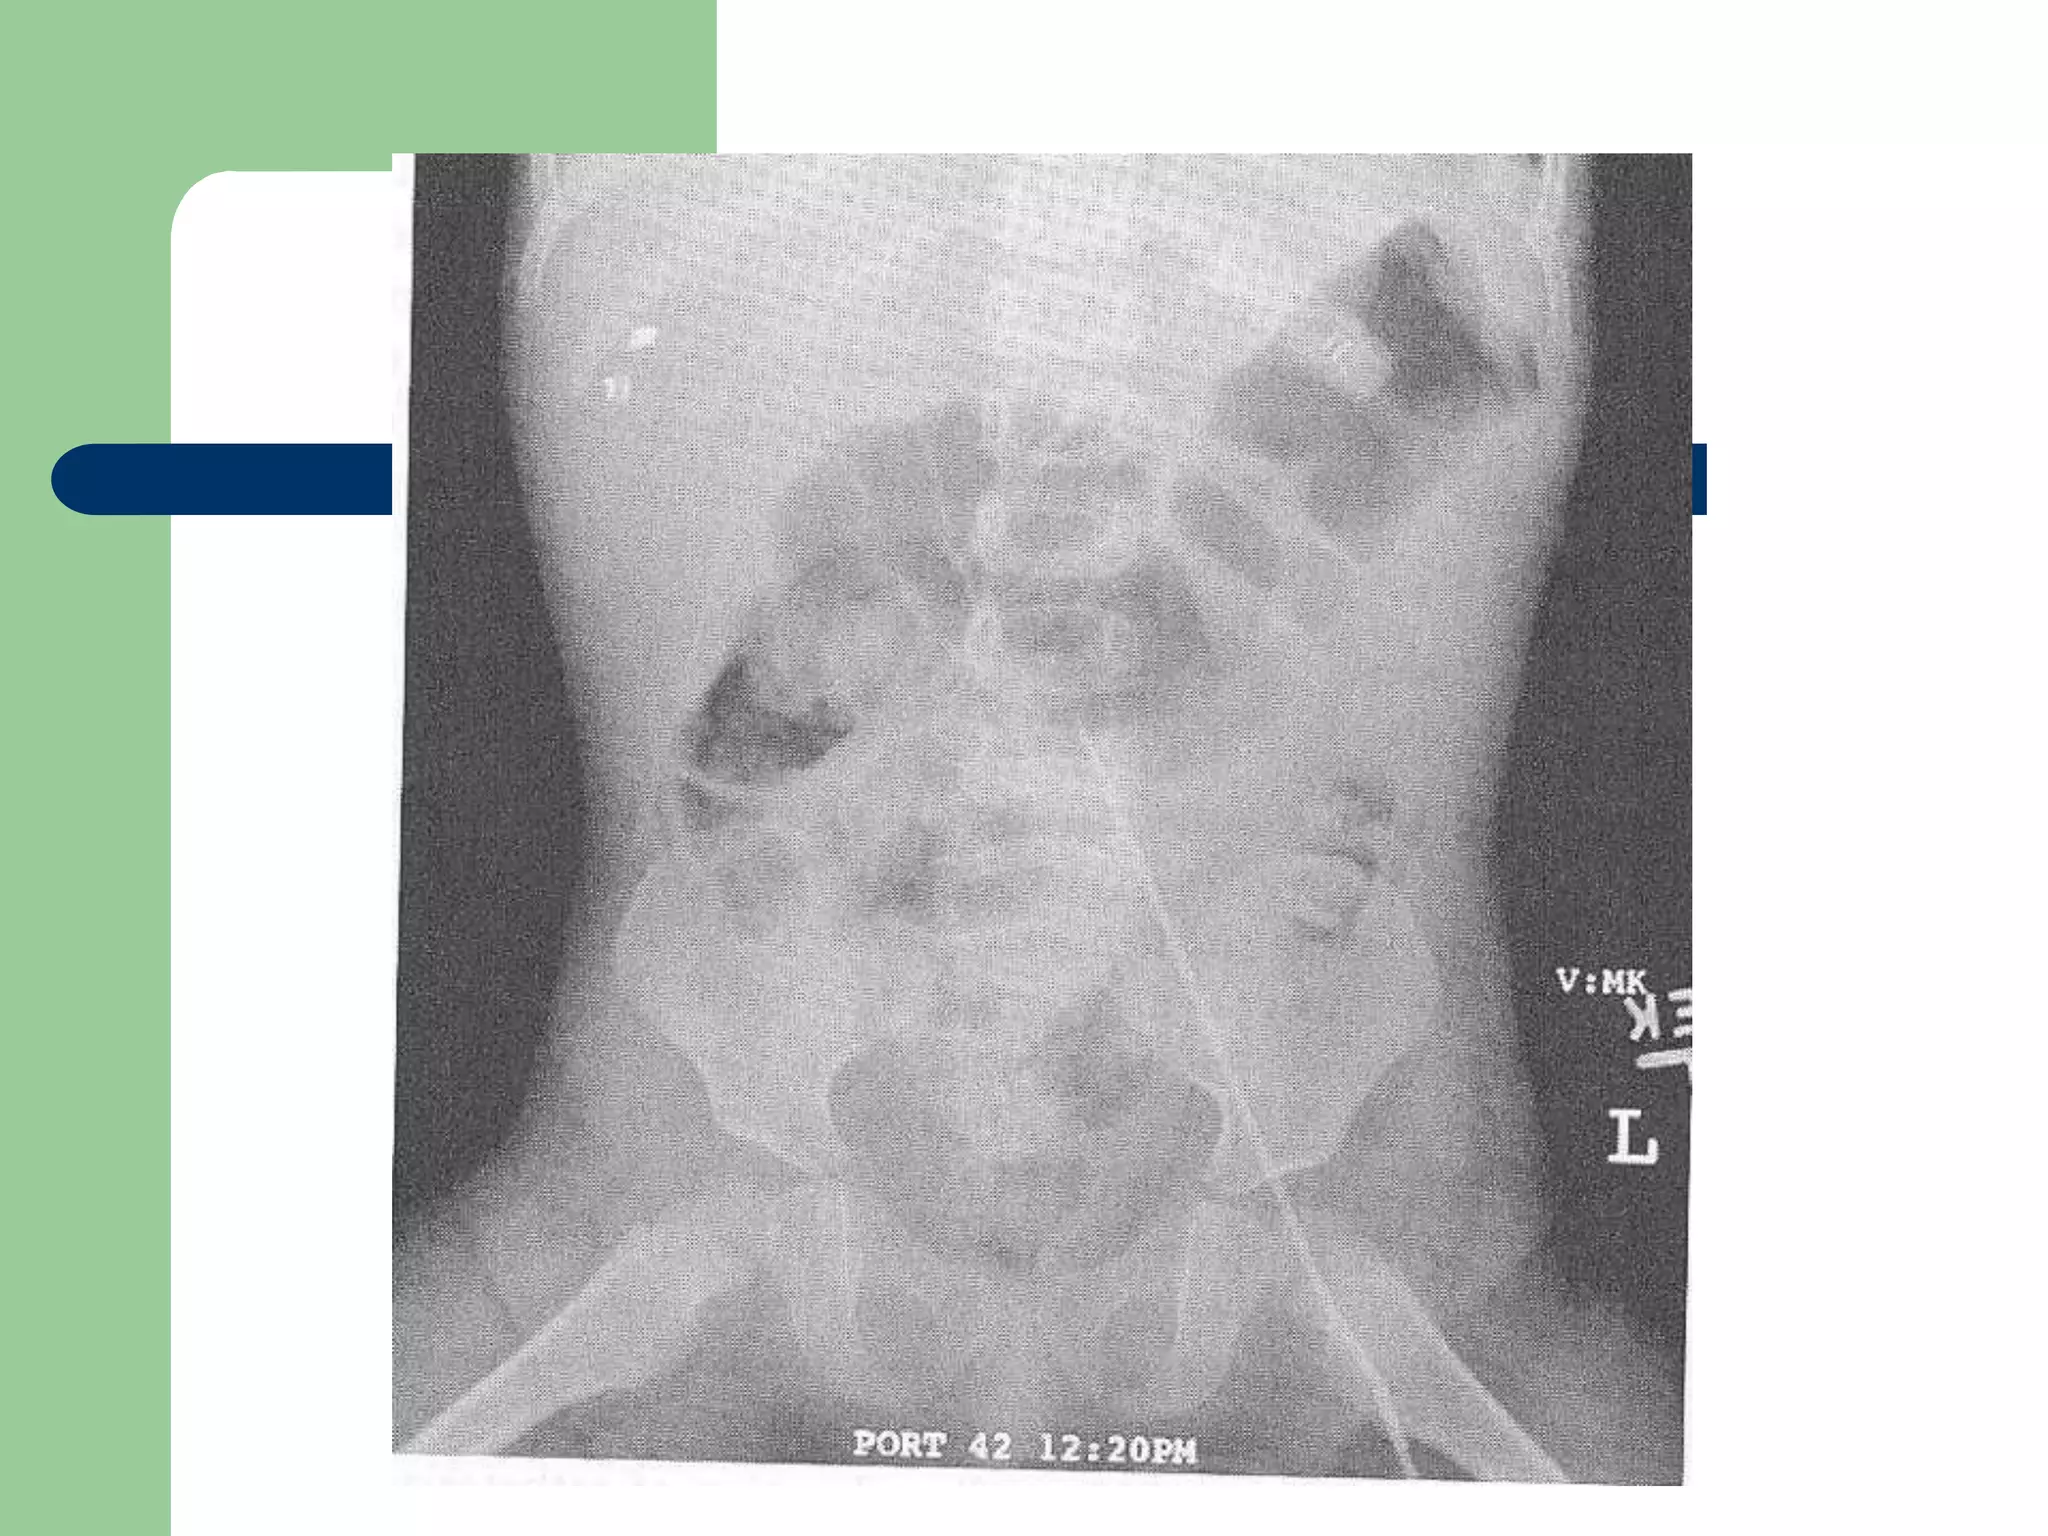

Seldinger Technique

Procedure

 Blood flash - Insert wire

– Wire not going smoothly

 Needle no longer in vessel

 False tracking in subcutaneous tissue

 Thrombus

 Advancing into lumbar veins

 Small incision

– Blade directed away from wire

 Twisting motion of dilation

 Remove dilator

 Advance catheter

 Remove wire

 Aspirate and flush all ports

 Secure line with sutures

 Sterile dressing